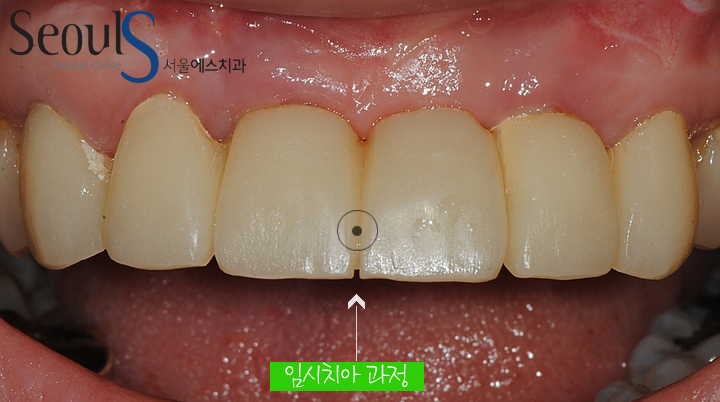

임시 치아를 결합한 모습입니다

임시 치아는 수정과정을 거치게 되며

환자분과 결합 될 치아의 모양과 색에 대해 충분히 이야기를 한 후

환자분도 만족하고 병원도 만족할수 있는 치아를 제작 및 결합하게 됩니다